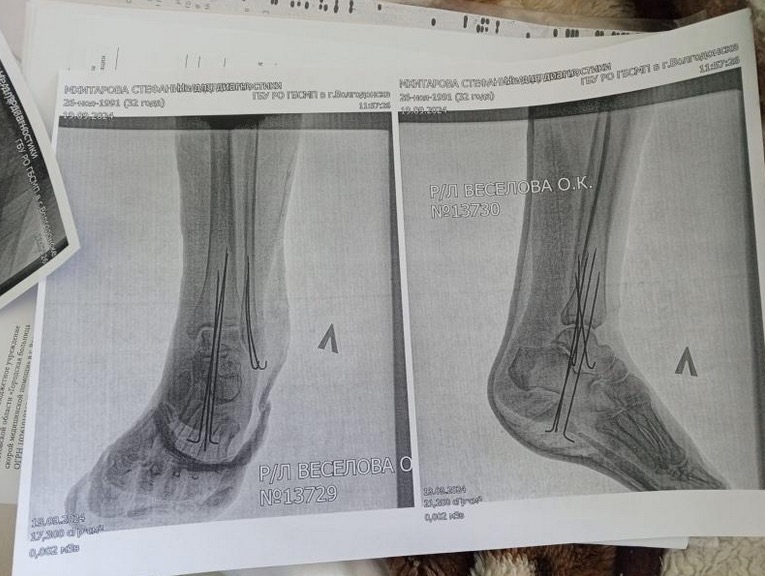

После падения Стефания оказалась в больнице: у нее был сломан голеностоп, вставлены спицы, проведена операция. Около месяца она провела под наблюдением врачей. «У меня такие планы были на жизнь! Явно не вот это вот. У меня есть стабильная работа с карьерным ростом, я могла вырасти как-то, жить нормально. А теперь я лежу тут [в больнице] и не могу ничего сделать, а у меня ипотека, как теперь ее выплачивать», — рассказала «Блокноту» пострадавшая.